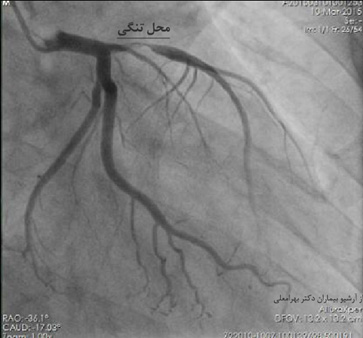

به این ترتیب با رگ گیری از دست یا پای بیمار، متخصص قلب یک لوله باریک به نام کاتاتر را وارد شریان اصلی بیمار می کند و آن را به عروق کرونر قلب در ابتدای آئورت می رساند. سپس ماده حاجب را از این طریق به درون شریانها تزریق می کند تا تصاویر عروق کرونر به دست آید. چنانچه تنگی یا انسدادی در محلی از رگ وجود داشته باشد در تصاویر مشخّص می شود و در مرحله بعد برنامه ریزی درمانی صورت می گیرد.